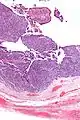

| Micrograph of transitional cell carcinoma of the ovary. H&E stain. |

Transitional cell carcinoma of the ovary (TCC of the ovary) is a rare type of ovarian cancer that has an appearance similar to urothelial carcinoma (also known as transitional cell carcinoma).[1]

TCC of the ovary is diagnosed by examination of the tissue by a pathologist. It has a characteristic appearance under the microscope and distinctive pattern of immunostaining.[2]